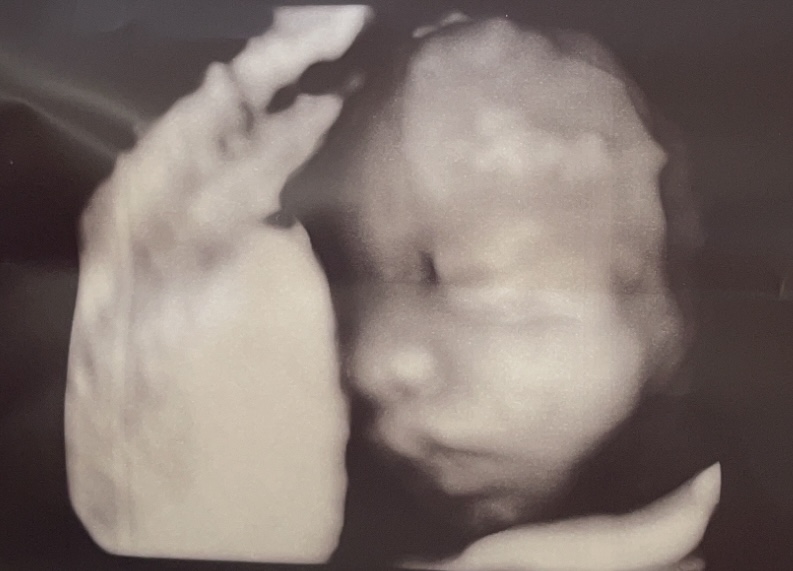

添付のエコー経過写真、以下が気になりますが

専門家の先生はどう見られますか?

・耳が折れ曲がっている?(指摘はなし)

・鼻がまんまる(低い?)

・口のぷっくり具合(口唇口蓋裂?)

・目の腫れぼったさ(指摘はなし、胎児はこんなものとの事)

エコーのお写真を拝見いたしました。

エコーの写真でもありますので、赤ちゃんが動いている瞬間を取りおさえたものになります。

多少ぶれることもあると思います。

拝見させていただく限りでは、目や鼻、口や耳とこのような感じになるのかな?特に異常がこのお写真だけではなさそうには感じました。

はっきりとしたお返事をさせていただくことは難しいように思うのですが、また先生にもご相談いただけたらと思います。